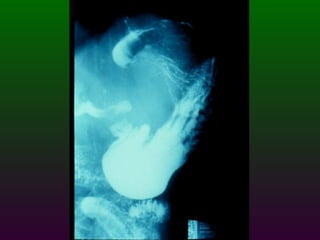

SEGD ENFERMEDADES DEL ESTÓMAGO Y DUODENO DIVISIÓN ANATÓMICA DEL ESTÒMAGO CARDIAS  FONDO CUERPO  ANTRO  PÍLORO

SEGD ENFERMEDADES DEL ESTOMAGO Y DUODENO El duodeno se divide en cuatro porciones; que se extienden desde el píloro hasta el ligamento de Treitz. La primera porción se denomina bulbo duodenal.

SEGD ENFERMEDADES DELESTÓMAGO Y DUODENO DIVISIÓN ANATÓMICA DEL ESTÒMAGO CARDIAS FONDO CUERPO ANTRO PÍLORO

SEGD ENFERMEDADES DELESTOMAGO Y DUODENO El duodeno se divide en cuatro porciones; que se extienden desde el píloro hasta el ligamento de Treitz. La primera porción se denomina bulbo duodenal.